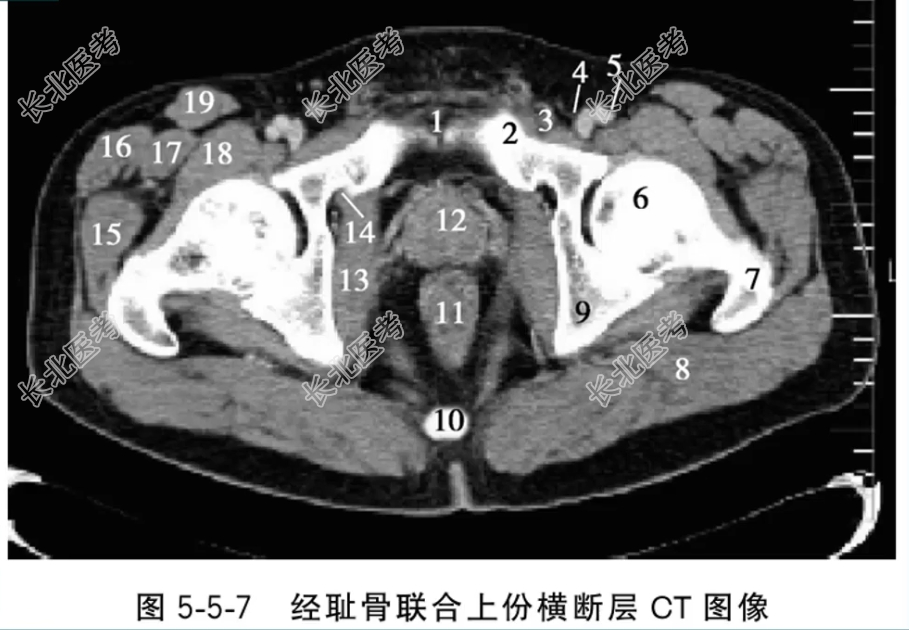

- 单项选择题经耻骨联合上份横断层CT图像中,标记为12的结构是

A、耻骨联合

B、前列腺

C、直肠

D、闭孔内肌

E、股骨头